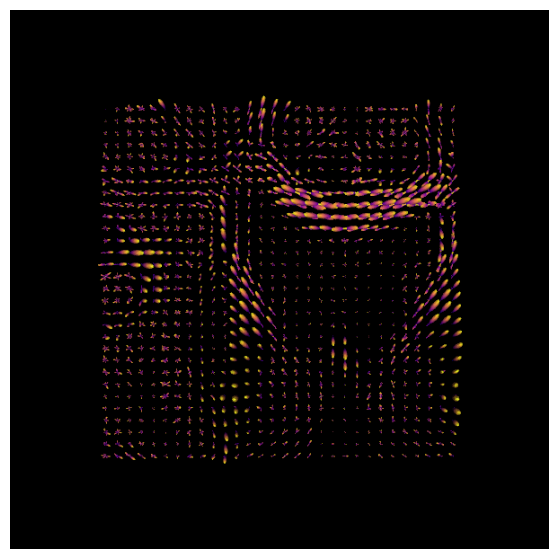

After estimating a response function, we can start the deconvolution process with fitting CSD model to the data.

# Set up the scene for visualization

scene = window.Scene()

# Fit the CSD model to the data

csd_model = ConstrainedSphericalDeconvModel(gtab_ap, response)

# Fit on a smaller portion of the data (optional for faster computation)

data_small = data[30:60, 40:70, 29:30]

csd_fit = csd_model.fit(data_small)

csd_odf = csd_fit.odf(default_sphere)

fodf_spheres = actor.odf_slicer(csd_odf, sphere=default_sphere,

scale=0.9, norm=False,

colormap='plasma')

scene.add(fodf_spheres)

csd_odfs = window.snapshot(

scene, fname=os.path.join(os.getcwd(), 'csd_odfs.png'), size=(600, 600),

offscreen=True)

fig, axes = plt.subplots(figsize=(7,7))

axes.imshow(csd_odfs, cmap="plasma")

axes.axis("off")

plt.show()

With DIPY’s peaks_from_model the peak directions (maxima) of the ODFs can be found. We will visualize both the ODFs and peaks in the same space:

csd_peaks = peaks_from_model(model=csd_model,

data=data_small,

sphere=default_sphere,

relative_peak_threshold=.5,

min_separation_angle=25,

parallel=True,

num_processes=10)

scene.clear()

fodf_peaks = actor.peak_slicer(csd_peaks.peak_dirs, peaks_values=csd_peaks.peak_values)

scene.add(fodf_peaks)

fodf_spheres.GetProperty().SetOpacity(0.6)

scene.add(fodf_spheres)

csd_both = window.snapshot(

scene, fname=os.path.join(os.getcwd(), 'csd_both.png'), size=(600, 600),

offscreen=True)

fig, axes = plt.subplots(figsize=(7,7))

axes.imshow(csd_both, cmap="plasma")

axes.axis("off")

plt.show()